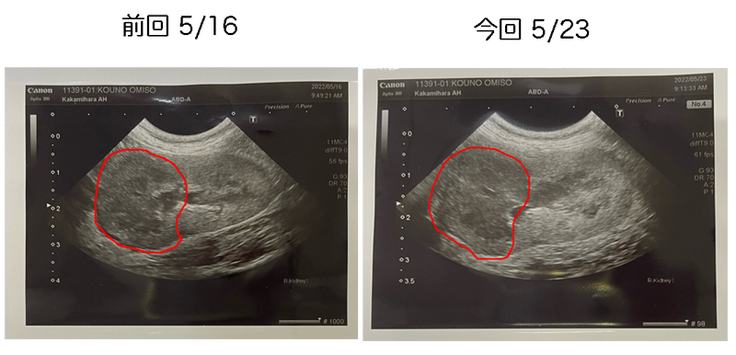

肝心の腫瘍の方は、ほんの僅かながら小さくなった部分もあるようですが、抗がん剤に対しての抵抗力が強く、やはり強固な腫瘍のようです。